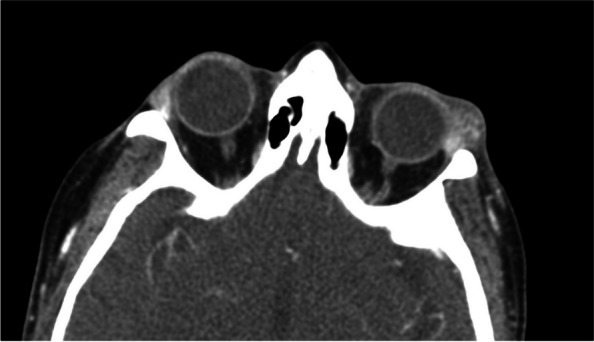

Evaluation of complete blood count, erythrocyte sedimentation rate, C-reactive protein, antinuclear antibodies, angiotensin converting enzyme, anti-Sjogren’s syndrome A, anti-Sjogren’s syndrome B, rheumatoid factor, and immunoglobulin G were all normal. Perinuclear anti-neutrophil cytoplasmic antibodies were elevated, but myeloperoxidase anti-neutrophil cytoplasmic antibodies and proteinase-3 antibodies were normal. CT revealed left lacrimal gland enlargement (Fig. 2).

Fig. 2.

Axial CT scan of the orbits depicting left sided lacrimal gland enlargement